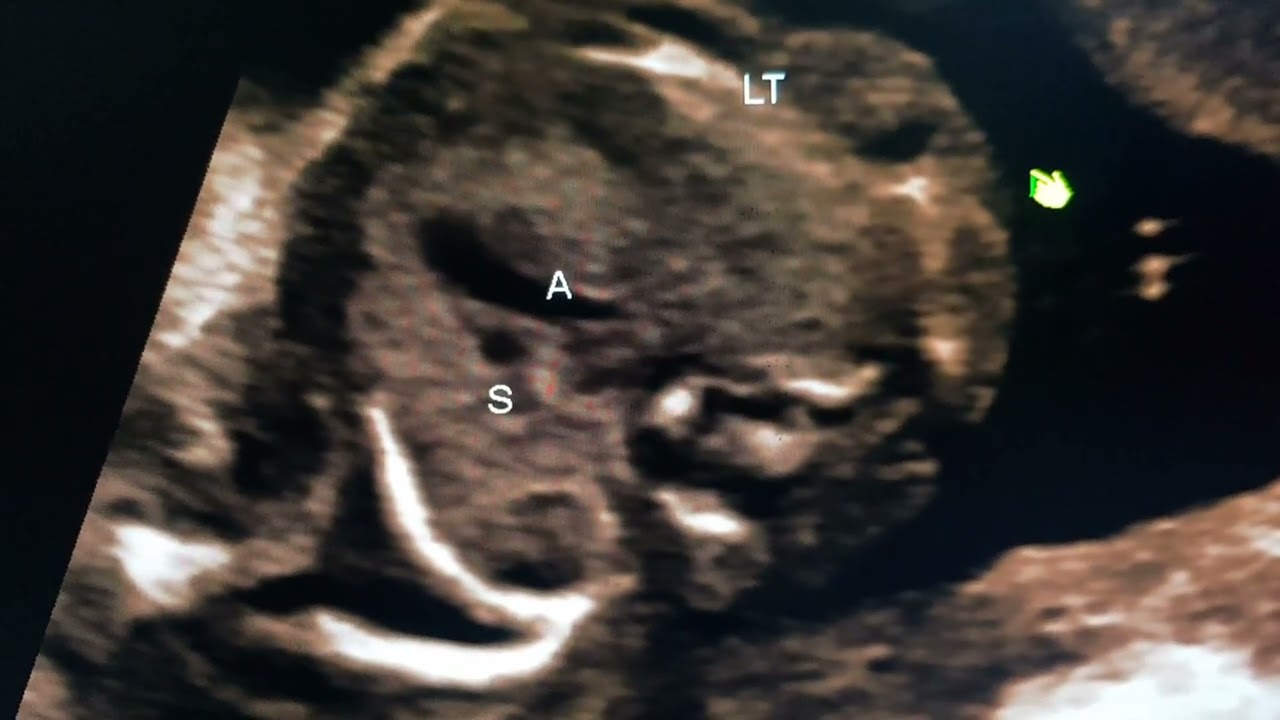

Урок по фетальной нейросонографии, проводимый доктором Прадипом в рамках серии «Refer».

Описание: Обучение проведению фетальной нейросонографии в случае двусторонних кист сосудистого сплетения.